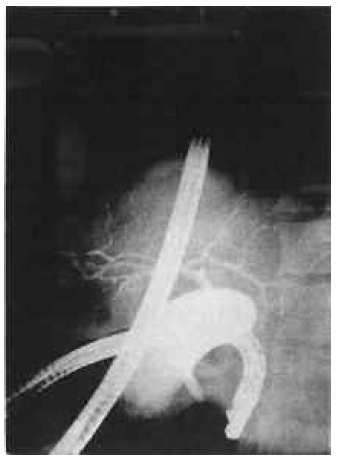

During the preoperative period, complete clinical, laboratory, and radiologic examinations were done for both the donor and the recipient. Radiologic and angiographic evaluations of the recipient showed that the portal system and hepatic arterial system were patent (Figure 3). Donor hepatic arteriography and endoscopic retrograde cholangiography showed the left hepatic branches to lie in correct anatomical positions (Figures 4, 5). HL A- A, -B, and -DR typing showed one haplotype matching. After the crossmatch, which resulted as negative, a segmental liver transplantation from the living donor was performed on April 29, 1999. The technique of the donor and recipient operations was about the same as in case 1, with the exception of the stabilization of the transplanted liver, which was provided by pulling the tissue expander in the right subdiaphragmatic area. During left lateral segmentectomy of the donor, no blood was used for the donor operation; however, 4 units of blood were transfused to the recipient.

Figure 3. Recipient hepatic angiogram showing normal anatomical structure.

Figure 4. Donor hepatic angiogramshowing normal arterial structure.

Figure 5. Endoscopic retrograde cholangiogram showing normal bile systemin the donor.